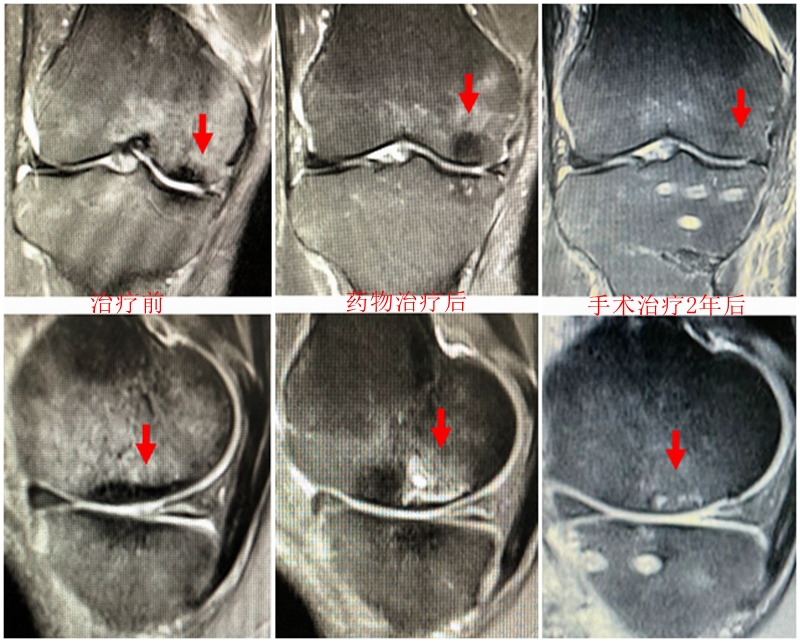

病例3:男,70岁,主诉右膝关节疼痛1年余。查体右膝无肿胀畸形,膝活动度0-120°,内侧间隙压痛。

已经累及44%的股骨内侧髁病变,半月板轻度突出,内侧后角水平撕裂

MRI上深度>20mm

治疗选择保守还是手术?

保守治疗4个月后复查

保守治疗后效果欠佳,坏死范围扩大、塌陷

翻修手术选择截骨矫形还是单髁置换?

最终选择截骨矫形

术后1年1个月

术后2年1个月拆钉

内侧半月板突出未见明显进展